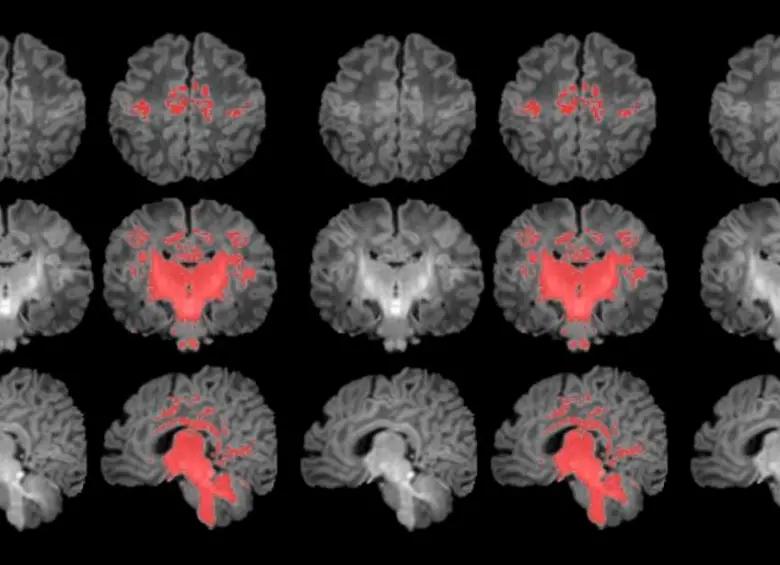

La contaminación del aire durante el embarazo retrasa la maduración del cerebro en los recién nacidos

Así lo concluyó un estudio publicado en la revista Environment International, en el que los investigadores observaron qu...